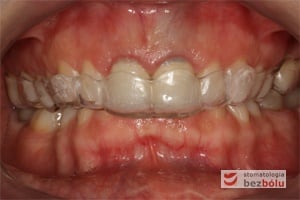

Pozycjonery to system przezroczystych nakładek precyzyjnie dopasowanych do łuków zębowych pacjenta, które przesuwają zęby w odpowiednio zaplanowane i wyznaczone przez lekarza ortodontę miejsca. Stanowią one alternatywne rozwiązanie dla aparatów stałych i ruchomych, jakkolwiek zakres wskazań do ich stosowania jest mocno ograniczony w porównaniu z aparatami stałymi. Są wykonywane indywidualnie dla każdego pacjenta, przez wykwalifikowanego technika dentystycznego.

- Natłoczenie szyny metodą termoformingu w zależności od metody leczenia dokonujemy wyboru płytki o odpowiedniej grubości (1,0 standardowo ). Materiałem, z którego wykonywane są nakładki jest erkodur.